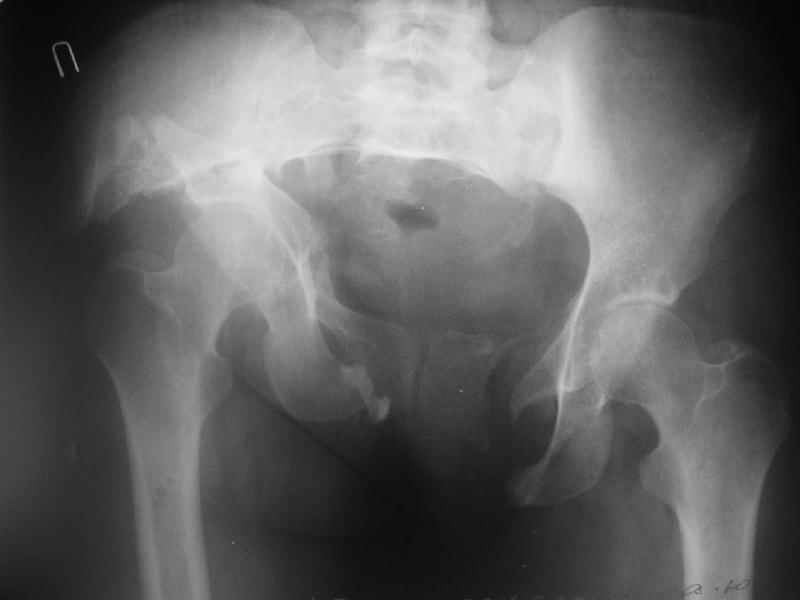

Снимки до лечения: